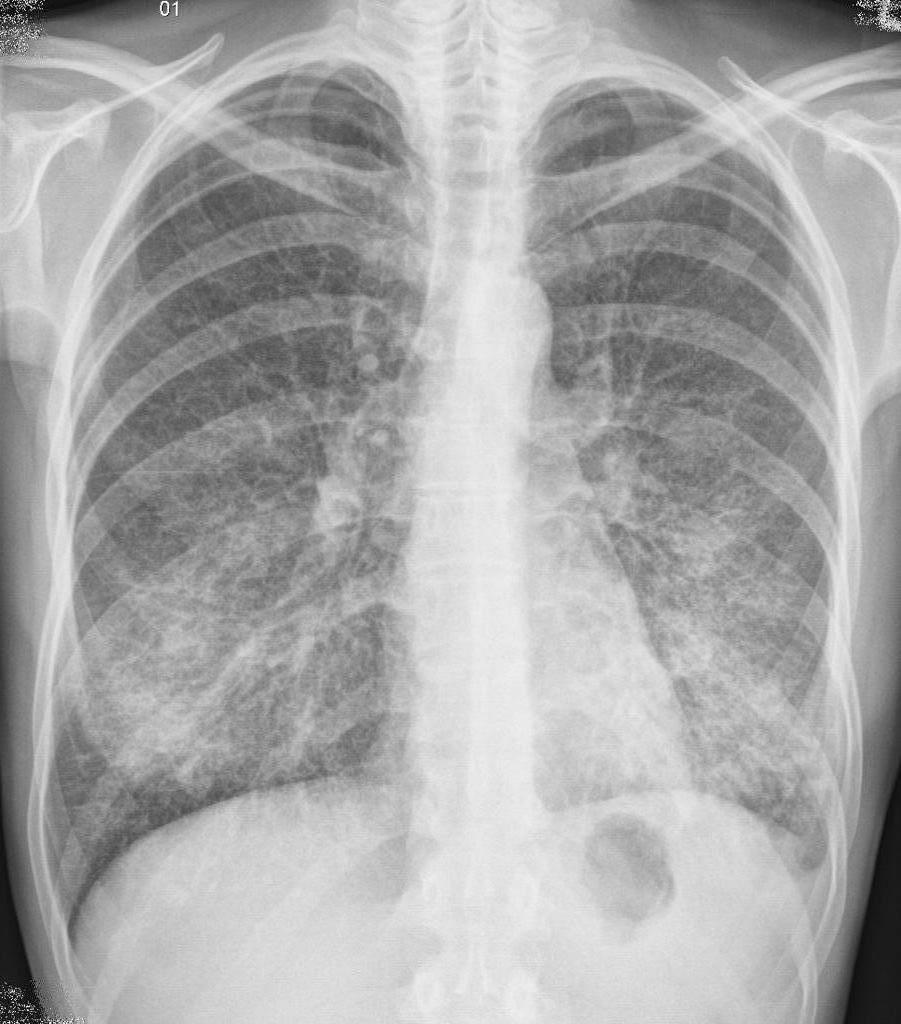

Usually the disease begins acutely, a cough appears with mucopurulent sputum. During the examination, shortening of percussion sound, weakening of bronchial breathing, moist small-bubbling rales, crepitus are noted. In blood tests, leukocytosis is observed. X-rays show zones of infiltration.

To clarify the diagnosis, the following diagnostic procedures can be performed:

- Roentgenography.